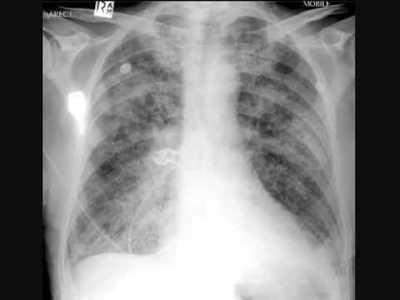

Quais são os sinais radiológicos evidenciados no edema agudo de pulmão:

Answer

• Cefalização da trama vascular e espessamento de linhas sagonais

• Congestão perihilar e bibasal e espessamento de linhas B de Kerley

• Borramento algodonoso bilateral e difuso edema pericárdico

• Edema alveolar e afinamento de cisuras interlobares

Numa radiografia de tórax, quando se evidencia desvio homolateral do mediastino, sugere-se:

• Atelectasia.